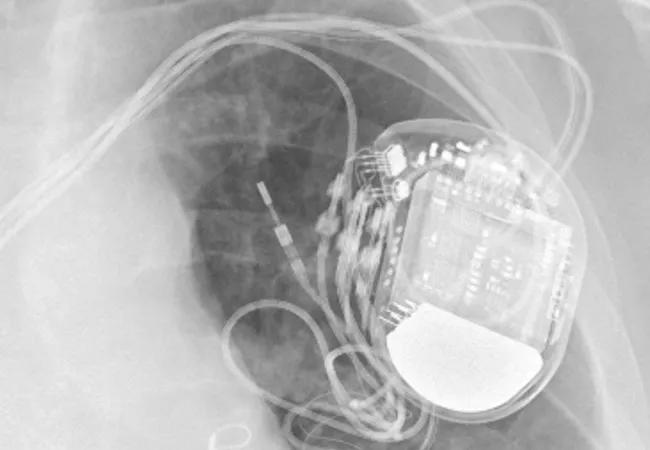

“The first clinic visit takes about two hours,” Dr. Rickard notes. To evaluate biventricular pacing, the patient has an electrocardiogram with and without CRT pacing. Device positioning of the left ventricular lead is checked on chest radiographs. Laboratory tests (standard electrolyte and renal panel, complete blood count) are performed to determine if anemia or renal dysfunction is involved.

“We perform a comprehensive device interrogation,” Dr. Rickard explains. “That includes assessment of battery status, lead impedances and thresholds, heart rate and activity histograms, percentage of atrial and ventricular pacing, and the presence of atrial and ventricular tachyarrhythmia.” Echocardiographic measures are averaged from at least three consecutive cycles, in conformance with American Society of Echocardiography guidelines.